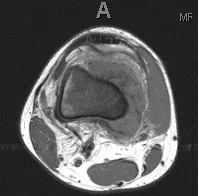

This 18 year old boy had pain in his knee that was not going away over a period of months. Eventually X-rays were done (first image on the left) which show the hallmark findings of osteosarcoma. As seen more closely on the second image, there is a mass adjacent the bone which is calcified. This is almost definitive for osteosarcoma. The last two are MRI images showing the tumor extending up and outside the femur. His tumor was localized to the femur (Stage IIb).